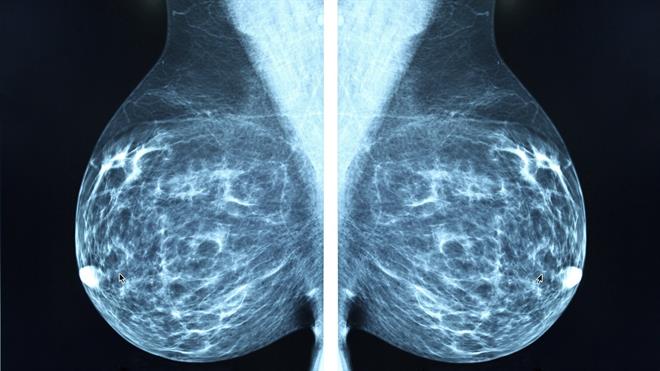

تیمێکی نێودەوڵەتی لە توێژەران و زانایانی بواری پزیشکی، وەرچەرخانێکی گەورەیان لە بواری تەکنەلۆژیای تەندروستیدا ڕاگەیاند، ئەویش پەرەپێدانی سیستمێکی پێشکەوتووی ژیری دەستکردە کە توانایەکی بێوێنەی هەیە لە دەستنیشانکردنی زووی جۆرە جیاوازەکانی شێرپەنجە. ئەم ئامرازە نوێیە وەک هیوایەکی گەورە بۆ ملیۆنان کەس لە جیهاندا دەبینرێت، چونکە دەتوانێت نیشانە سەرەتاییەکانی نەخۆشییەکە لە قۆناغێکدا بناسێتەوە کە هێشتا هیچ نیشانەیەکی دیار لە جەستەی نەخۆشەکەدا دەرنەکەوتووە و ڕێگاکانی تاقیگەیی باو ناتوانن هەستی پێ بکەن.

ئەم سیستمە تەنها پشت بە یەک جۆر پشکنین نابەستێت، بەڵکو لە یەک کاتدا چەندین داتای جیاواز وەک وێنەگرتنی پزیشکی (تیشک و سۆنەر)، نیشاندەرە بایۆلۆژییەکانی ناو خوێن، و مێژووی وردی تەندروستی نەخۆشەکە شیکار دەکات. ئەم شێوازی شیکردنەوەیە ڕێگە بە ژیری دەستکردەکە دەدات ئەو گۆڕانکارییە زۆر ورد و "شاراوە"یانە بدۆزێتەوە کە زۆرجار لەلایەن چاوی پزیشکە پسپۆڕەکانیشەوە فەرامۆش دەکرێن یان بە ئاسانی نابینرێن. تاقیکردنەوە سەرەتاییەکان دەریانخستووە کە ئەم ئامرازە دەتوانێت هەندێک جۆری شێرپەنجە تا سێ ساڵ زووتر لەو کاتەی کە ڕێگاکانی ئێستا دەستنیشانی دەکەن، ئاشکرا بکات.

ئەنجامە بڵاوکراوەکان ئاماژە بەوە دەکەن کە ئەم تەکنەلۆژیایە بە شێوەیەکی تایبەت لە دەستنیشانکردنی شێرپەنجەکانی پەنکریاس، هێلکەدان و سییەکاندا سەرکەوتنی گەورەی بەدەستهێناوە. ئەم سێ جۆرە شێرپەنجەیە بەوە ناسراون کە زۆرجار کاتێک دەدۆزرێنەوە کە گەیشتوونەتە قۆناغی کۆتایی و ڕێژەی ڕزگاربوون لێیان نزمە. ئەو نەخۆشخانانەی کە بەشدارییان لە پرۆگرامە تاقیکارییەکاندا کردووە، ڕاپۆرتیان داوە کە ئەم سیستمە دەبێتە هۆی کەمکردنەوەی بەرچاوی پێویستی بە نەشتەرگەرییە وردەکانی لابردنی نموونە (Biopsy) کە بۆ نەخۆش تێچووی زۆر و ئازاری جەستەیی هەیە، لە هەمان کاتدا چانسی سەرکەوتنی چارەسەرەکان بۆ چەندین هێندە بەرز دەکاتەوە.

بۆ ماوەیەکی درێژ، دەستنیشانکردنی شێرپەنجە تەنها پشتی بە ئامێرە تیشکییەکان و ڕێکارە پزیشکییە جەستەییەکان دەبەست، کە جگە لە گرانبەهاییەکەی، گوشارێکی دەروونی قورسی بۆ سەر نەخۆشەکان دروست دەکرد و زۆرجاریش درەنگ دەگەیشتنە ئەنجام. هەرچەندە لە دەیەی ڕابردوودا فێربوونی ئامێر (Machine Learning) یارمەتیدەر بووە لە باشترکردنی وردی پشکنینەکان، بەڵام ئەم سیستمە نوێیە بە گشتگیرترین و زیرەکترین مۆدێلی دەستنیشانکردن لە مێژووی پزیشکیدا دادەنرێت کە تا ئێستا دروستکرابێت.